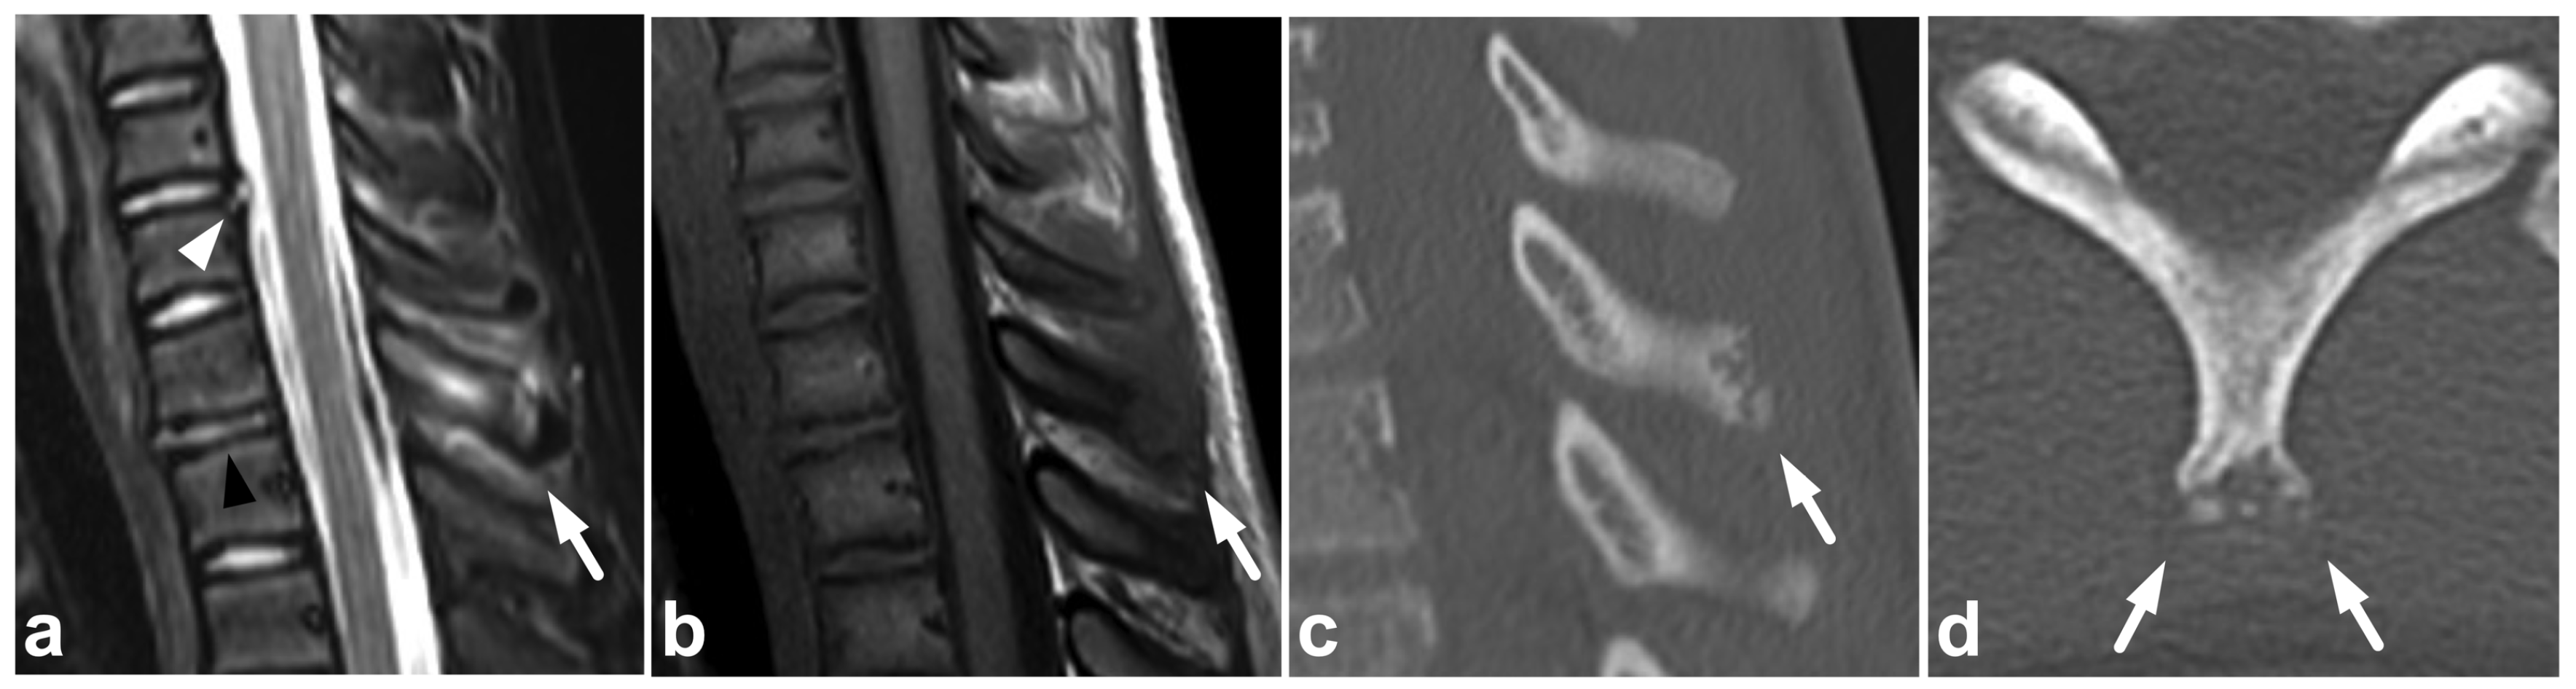

7.4. Imaging Appearances of Normal Skeletal Maturation